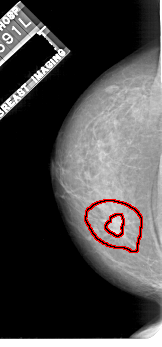

FILE: A_1112_1.LEFT_MLO.OVERLAY

TOTAL_ABNORMALITIES 1

ABNORMALITY 1

LESION_TYPE MASS SHAPE IRREGULAR MARGINS SPICULATED

ASSESSMENT 5

SUBTLETY 5

PATHOLOGY MALIGNANT

TOTAL_OUTLINES 2

BOUNDARY

CORE